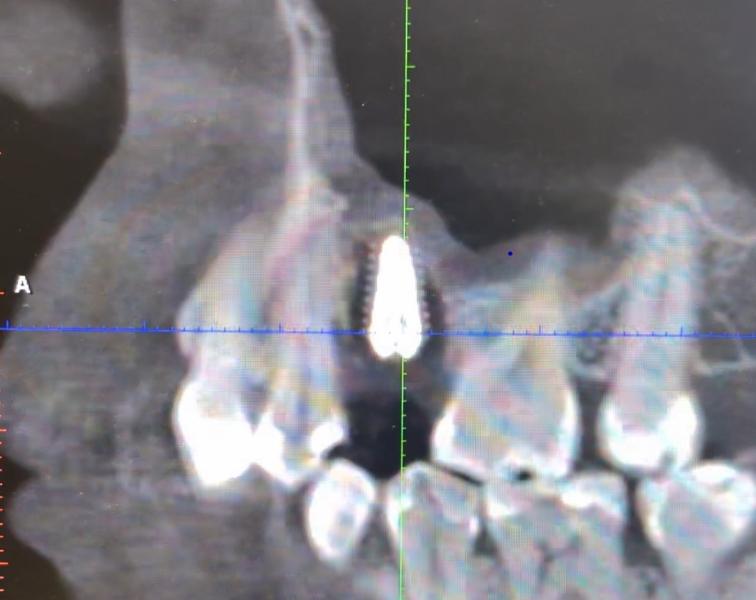

Мне сделали синус лифтинг 1,5 месяца назад, сейчас была в другой клинике и мне сказали что свищ хана, все удалять, заживлять и заново делать, не прижилось. И я это вижу на КТ. Ну по крайней мере у меня на работе если такая картина, то это плохо. Пишу своему имплантологу, скидываю видос КТ и она говорит, «ну ты же врач!!!!! Ты что не видишь????? У тебя заглушечный свищ, это нормально, все по плану, кость когда видна будет на КТ? Через полгода? ( этого вообще не поняла) Все нормально ходи дальше»

И я не понимаю, ну во первых я не понимаю что мне сделали изначально, может этот костный материал вокруг винта расположен и он рентген неконтрастный и он там пока не сформируется, его видно не будет. Или там реально вокруг винта гной и его надо удалять, пока до остеомиелита не дотянула и мне не отрежут пол верхней челюсти ( на что другой врач сказал вряд ли, но это мое лицо и мне не хотелось бы такого исхода)